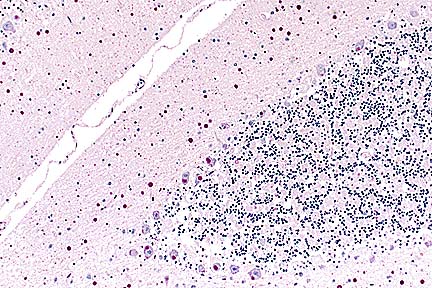

Numerous PAS-positive neuronal and glial inclusions in the cerebellum of a Maine Coon cat with tremors and seizure-like activity. (PAS, 100X, 65K)

Higher magnification of the field above, showing cytoplasmic inclusions within several Purkinje cells, as well as inclusions in unidentified cells in the molecular layer. (HE, 400X, 48K)

Contributor's Diagnosis and Comments: Cytoplasmic polyglucosan inclusions (Lafora bodies) within neuronal perikarya and processes, most numerous in Purkinje cells.

In sections of brain, there are few to many basophilic to amphophilic inclusions that occur within the cytoplasm of nerve cell bodies, neuronal processes, and scattered in the neuropil. These inclusions are usually round, range in size from 2 to 10 um diameter, and occasionally have a pale center or a thin, striated halo. These Lafora-like bodies are most numerous in the cerebellar molecular layers and within Purkinje cells, but are observed in all examined sections of brain.

Lafora bodies consist of complex polymers of glycoprotein, sometimes designated "polyglucosan bodies", and can occur within neuronal cell bodies or processes of the brain, spinal cord, or retinal ganglia. The round to globular basophilic cytoplasmic inclusions stain positively with PAS, alcian blue, and methenamine silver. In domestic animals, Lafora bodies have been observed most commonly in aging (at least 8 years of age) dogs and cats without apparent neurologic disease, but have also been described as incidental changes in some young animals. Lafora bodies have also been associated with a severe form of progressive myoclonus epilepsy in humans (juveniles) and dogs (young adult to middle-age), reflecting widespread intra-neuronal storage of these polyglucosans ("Lafora disease" or "neuronal glycoproteinosis"). The absence of other lesions to account for the observed neurologic signs incriminates the Lafora bodies as playing a role in the reported neurologic signs in this cat. In dogs with associated neurologic disease, the deposits are most commonly observed in Purkinje cells, similar to the distribution noted in this cat. In children with Lafora disease, other sites of polyglucosan deposition include skin and liver, and biopsies of these tissues have been used to help establish the diagnosis. Lafora bodies were not found in tissues from other than the CNS in this cat.

AFIP Diagnosis: Cerebellum, molecular and Purkinje cell layers: Polyglucosan bodies (Lafora bodies), neuronal and extracellular, diffuse, numerous, Maine-Coon, feline.

Conference Note: This case was also reviewed by AFIP's Department of Neuropathology. Lafora bodies are complex glycoprotein neuronal inclusions that can occur in the perikaryon, dendrites, or axons. They are PAS-positive and stain with alcian blue and methenamine silver. They can be found anywhere in the neuraxis and in retinal ganglion cells. Polyglucosan bodies have been associated with neurologic disease in humans, cats, dogs (Beagles, Basset Hounds, and Poodles), and a cockatiel. Lafora's disease in humans is a rare familial neurologic disorder of children. The disease is progressive and manifested by myoclonus. The characteristic histologic feature in the human disease is intraneuronal polyglucosan bodies, which occur predominantly in the substantia nigra and dentate nucleus. In dogs with neurologic disease attributed to the accumulation of intraneuronal polyglucosan bodies, the bodies are found predominantly within Purkinje cells and in thalamic neurons. In animals, Lafora bodies are frequently seen in the absence of neurologic disease. In these cases, the Lafora bodies can be found in any area of the brain and in the spinal cord.